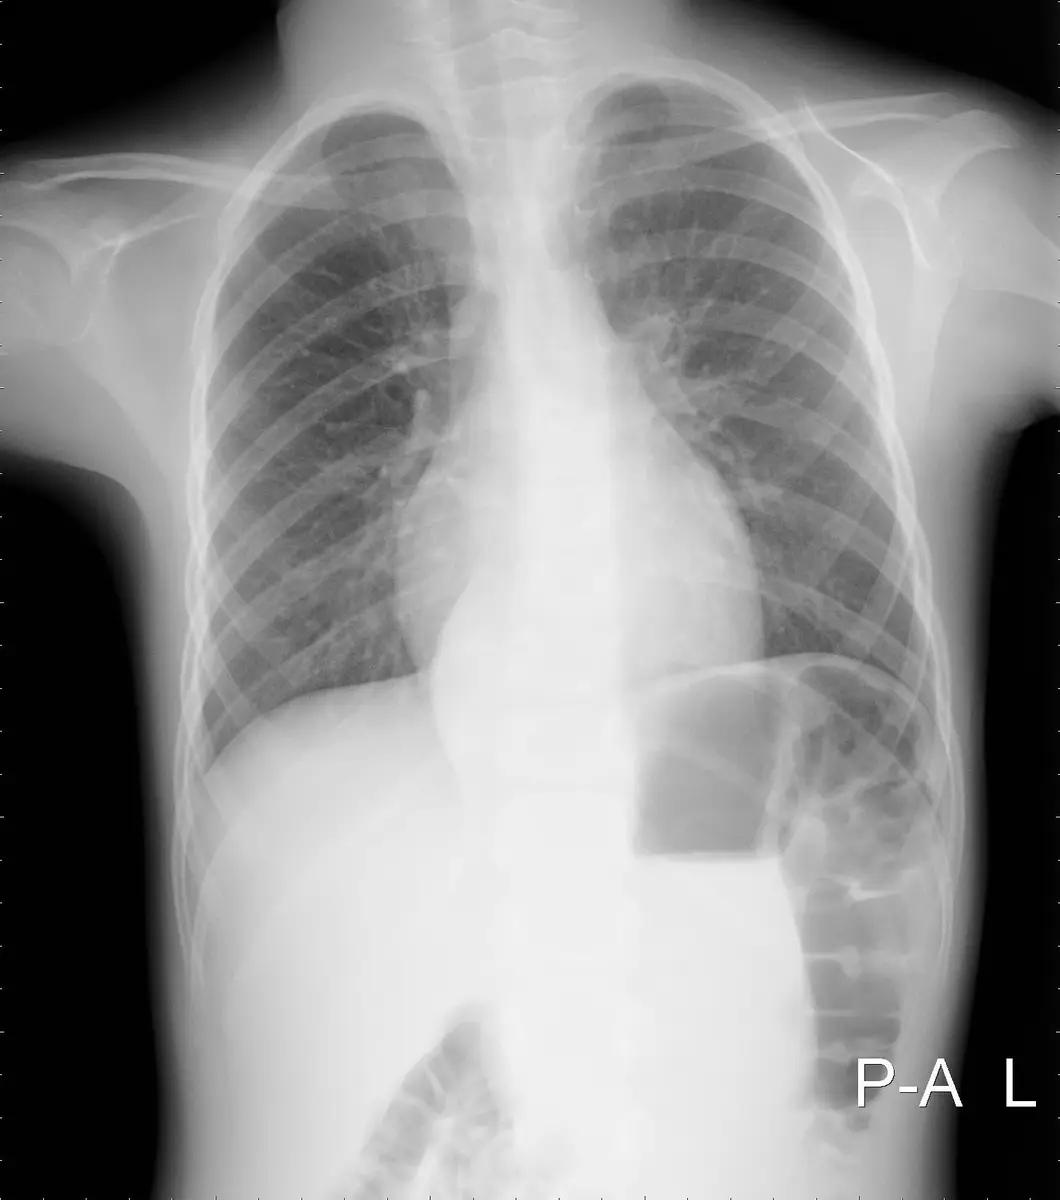

圖一(胸部 X 光正面,PA view): 右側後縱膈腔可見一個邊緣清晰、輪廓平滑的橢圓形高密度軟組織腫塊(soft tissue opacity),位於右側脊椎旁(paravertebral)區域,使右側脊柱旁線(paraspinal line)向外移位,呈現典型後縱膈腔腫瘤的影像特徵。整個腫塊與縱膈腔的交角為鈍角(obtuse angle),符合後縱膈腔腫瘤的表現。左肺野清晰,心臟大小正常。